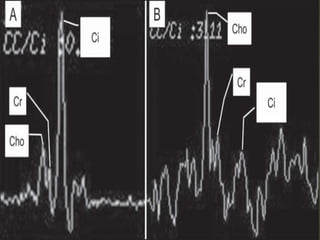

MR - SPECTROSCOPY

• Unique application of MRI that allows for the

relative quantification of tissue metabolites

within a preselected voxel of interest

• Choline (Cho), Creatine (Cr), and Citrate (Cit)

are the main metabolites measured with

proton spectroscopy in the prostate.

• Cho - phospholipid cell membrane component

that is increased in high turnover states.

Normal peak at 3.2ppm

• Cit - biochemical molecule produced by

normal prostate tissue. Normal peak at

2.6ppm

• Cr is involved in energy metabolism. Normal

peak at 3ppm.

USES OF MRS

• Tumor staging

• Determining tumor aggressiveness

• Evaluation of post-treatment recurrence

• Helpful for distinguishing prostate

adenocarcinoma from benign entities